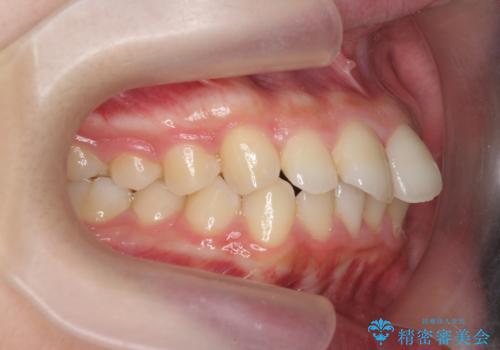

出っ歯を治すマウスピース矯正

- 出っ歯のように見える前歯の角度を治したい、と矯正治療を希望され来院されました。

抜歯をせずにマウスピース矯正システムインビザラインを用いてしっかりと前歯の角度を改善していきます。

前歯の角度だけでなく内側に倒れ込んでいた奥歯もしっかり起こすことで咬合関係も理想的に仕上げています。